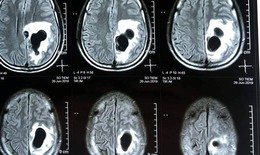

Ăn tiết canh, người đàn ông bị sán làm tổ trong não

SKĐS - Các bác sĩ Bệnh viện Hữu nghị Đa khoa Nghệ An vừa tiếp nhận nam bệnh nhân phát hiện có sán trong não do thói quen ăn tiết canh.

SKĐS - Theo TS. Nguyễn Văn Lâm – Trưởng khoa Truyền nhiễm, BV Nhi Trung ương, sán làm tổ trong não sẽ gây ra hiện tượng co giật và kéo theo nhiều biến chứng nghiêm trọng về sau. Còn với trẻ em sẽ làm ảnh hưởng tới vấn đề học tập và khả năng phát triển của não bộ, đồng thời cũng có thể gây ra những cơn co giật, ngất xỉu đột ngột.